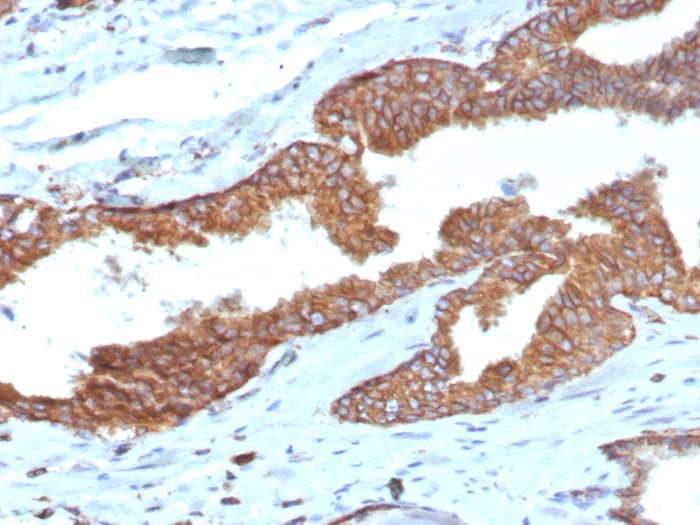

![Immunohistochemistry-Paraffin: COX-2 Antibody (COX2/3320R) - Azide and BSA Free [NBP3-08301] Immunohistochemistry-Paraffin: COX-2 Antibody (COX2/3320R) - Azide and BSA Free [NBP3-08301]](https://resources.bio-techne.com/images/products/COX-2-Antibody-COX2-3320R-Azide-and-BSA-Free-Immunohistochemistry-Paraffin-NBP3-08301-img0001.jpg)